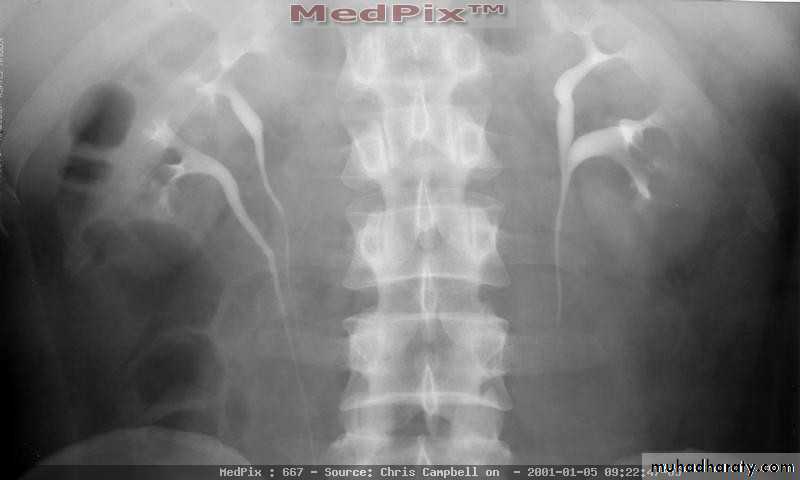

Crossed Renal Ectopia With and Without FusionHorseshoe Kidney

found in 1:1000 necropsies an is commoner in men.probably the most common of all renal fusion anomalies

The anomaly consists of two distinct renal masses lying

vertically on either side of the midline and connected at

their respective lower poles by a parenchymatous or fibrous

isthmus that crosses the midplane of the body.

Fusion of the renal masses early in embryonic life, so its ascent

will be impeded by inferior mesenteric artery.

The kidneys are low located, mal rotated and pelves lie anteriorly

Symptom When present, they are related to complications like hydronephrosis, infection, or calculus formation

Diagnosis ultrasound, IVU, CT scan

Treatment:

-Medical: pain relief and to control infection-Surgical: stone removal, PUJ stenosis correction and isthmus division in cases of

-operations on the aorta

Prognosis usually they have normal life.